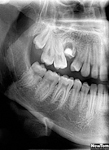

NewTom Giano

Jedná se o nejnovějším přístroj ze skupiny dentálních hybridních CBCT (3D) + 2D (pan i ceph) systémů. Opět umožňuje na základě jediného snímkování vytvořit všechny typy RTG zobrazení, které jsou pro lékaře potřebné. Používaná technologii tzv. „kuželového paprsku“ a speciální senzory pro minimální zátěž při snímkování pacienta.

Vyšetření pomocí tohoto přístroje (nebo 3D DVT - NewTom) a získaná data používáme pro každou implantaci, dále ve stomatochirurgii (zlomeniny čelistí, zuby moudrosti, cysty, onemocnění čelistního kloubu), ortodoncii (retinované zuby, nadpočetné zuby), parodontologii atd.